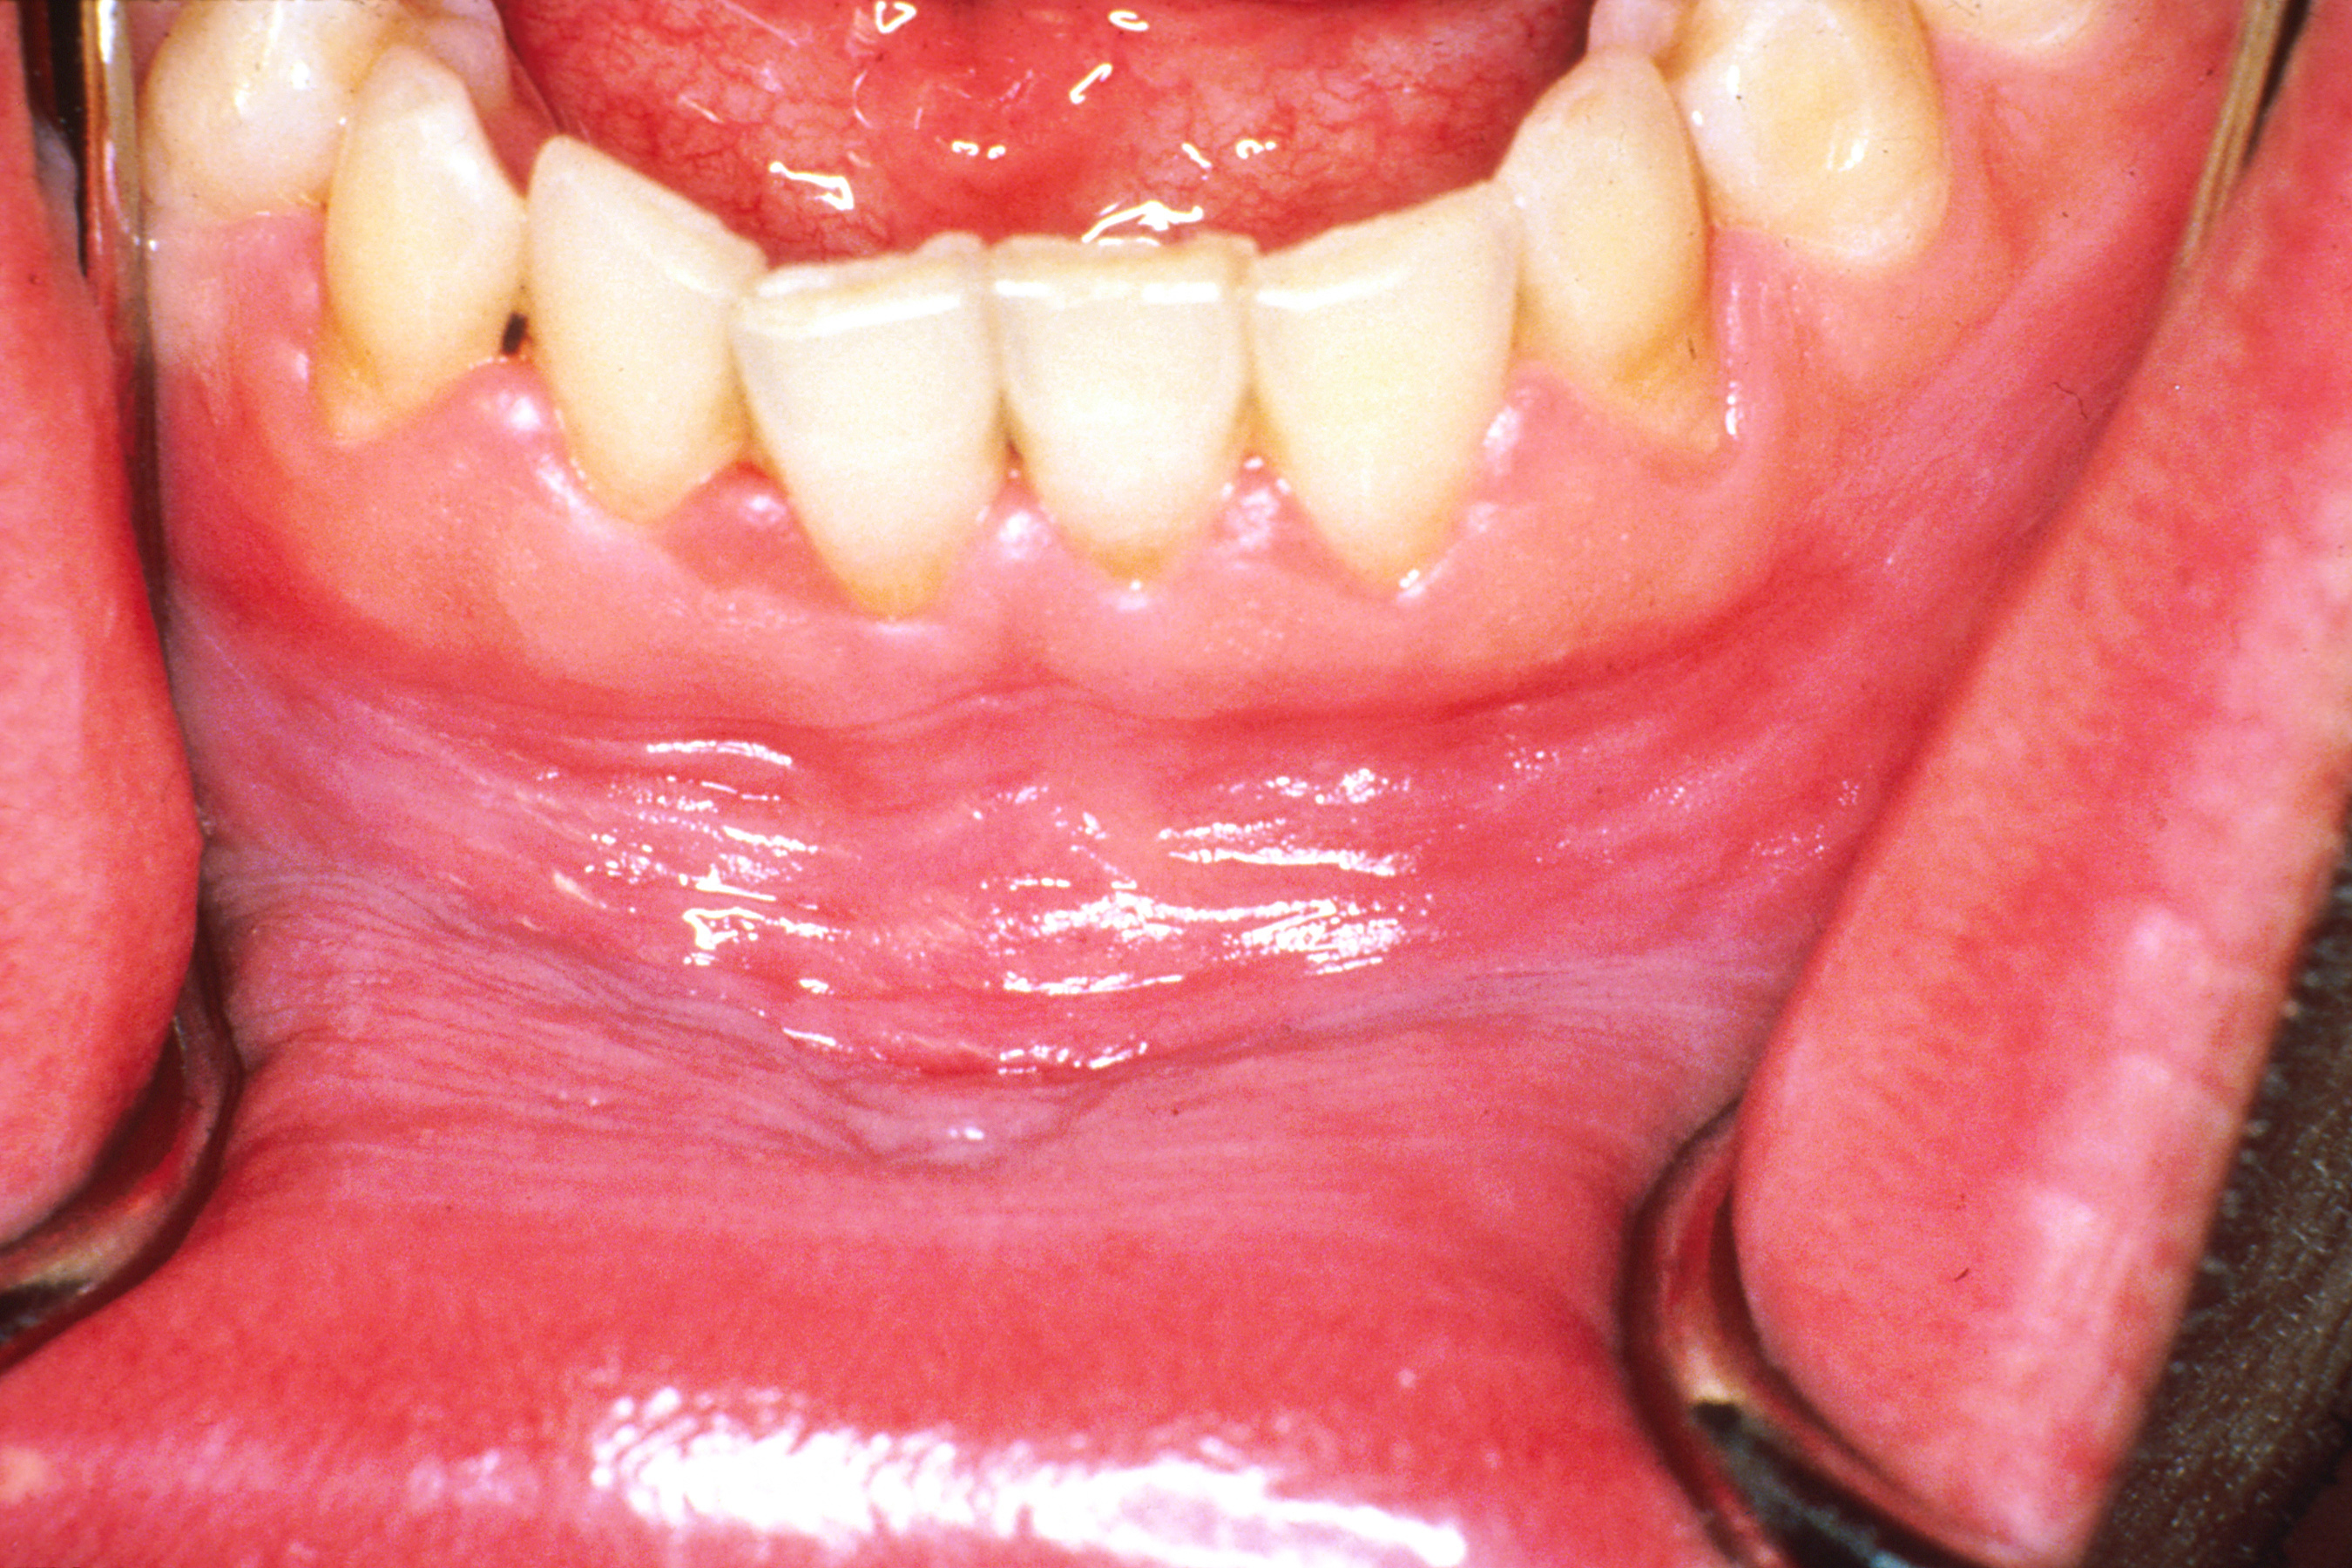

Hard or sharp food can cause an injury to the extra protrusion, leading. Learn more about burns on roof of mouth, second degree burns, skin pealing and pictures of the burnt palate. Even though many people may experience pain at the level of the palate, this does not mean that the problem the sooner you deal with the problem, the sooner you get back to your normal routine. Hopefully you'll like it as much as we do here. Picture based reference guides for anything and everything. This article provides you with a list of possible cause of. Bumps on roof of mouth are caused by various factors. Roof of mouth, palate, incisive canals, lesser palatine foramina, greater, lesser palatine vessels, palatine raphe, incisive papilla, palatine aponeurosis, palatine muscles, levator veli palatini, tensor veli palatini, uvular muscle, palatoglossus muscle, palatopharyngeus muscle Even the tiniest changes are often picked up by your tongue. This often seems to be after eating carby sharp food like pizza does anyone else have this? The roof of mouth feels bruised with a rough surface. The mouth, normally moist, is lined with a mucous membrane, and contains the teeth. On a day where your mouth is operating without issue i recommend you try this soup.

A look at the bump on roof of mouth, painful, hard, white, red, small bumps including the causes and how to get rid of it and the treatment. Its roof is formed by the hard palate at the front, and the soft palate at the back. Many people experience pain in their palate making the condition a common find despite the fact that the causes might differ. Hi i have soreness on the roof of my mouth. Hard or sharp food can cause an injury to the extra protrusion, leading. Painful bumps on roof of mouth. Small chips, a bump on the roof of your mouth, or even a tiny ulcer under your tongue are easy to pick out from the healthy or normal oral tissues around them. Normal roof of mouth photos. This article provides you with a list of possible cause of. Will i be given anything to control side effects? This often seems to be after eating carby sharp food like pizza does anyone else have this? However, you might feel pain on your. Gums may experience white patches more often.

The roof of the mouth is also known as the palate. Will i be given anything to control side effects? Using pipes to smoke can ultimately there is a protrusion on roof of the mouth and the side of the lower jaw. Your mouth is extremely sensitive. Below are pictures to illustrate the symptom. Gums may experience white patches more often. Small chips, a bump on the roof of your mouth, or even a tiny ulcer under your tongue are easy to pick out from the healthy or normal oral tissues around them. You will also find pictures throughout the page to distinguish the various causes and what they mean. Nutritional problems, such as vitamin b12, zinc, folic acid, or iron deficiency and gastrointestinal tract disease, such as coeliac disease and crohn's disease. When i make the n sound my tongue is on the roof of my mouth just before it slopes up to the pallet (gumline behind top front teeth) about the middle of my mouth from a left/right perspective and a bit forward from a front/back position. Picture based reference guides for anything and everything. On a day where your mouth is operating without issue i recommend you try this soup. Sores occur at the frontal portion of tongue, roof of the.